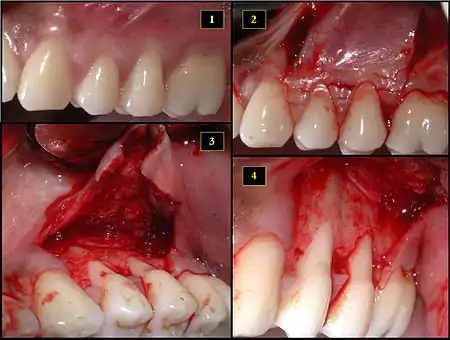

1. Recipient site exhibits gingival recession on both premolars and first molar (molar recession is not an esthetic issue and will not be treated)

2. Incisions prior to flap reflection

3. Full thickness flap elevated

4. Another viewpoint of the flapped recipient site